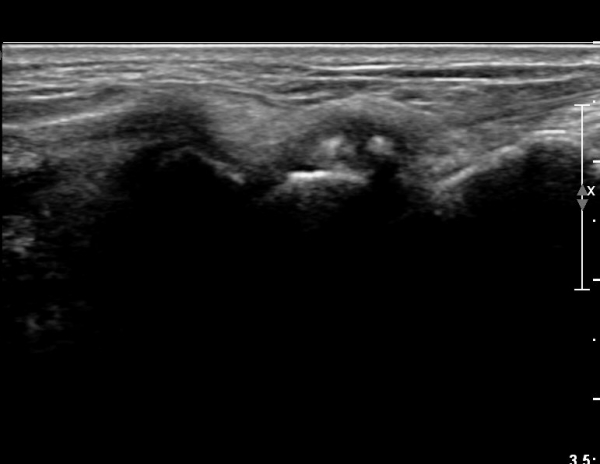

¼Õ¸ñ ¹èÃà, ̫̿ Á¾´Ü¸é°Ë»ç¿¡¼­ ô°ñ¼ö±Ù°ñ °üÀý³» ¼ö¾×Àú·ù¿Í »ï°¢°ñ Ç¥Ãþ¿¡ °ñ±ØÀÌ °üÂûµÈ´Ù(»çÁø 1),